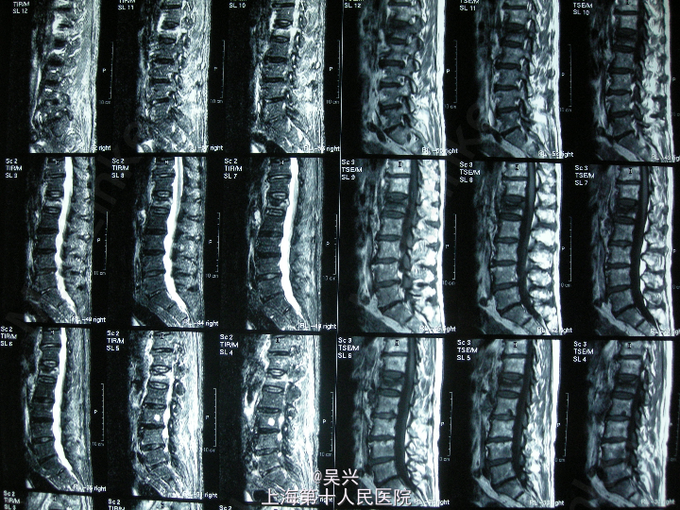

查体:L1棘突压痛,椎体叩击征(+),腰椎活动受限 辅查:X线、MRI片示L1椎体新鲜压缩性骨折

诊断:L1椎体压缩性骨折 处理:入院第二天局麻下行L1压缩性骨折椎体后凸成形术(PKP术)。